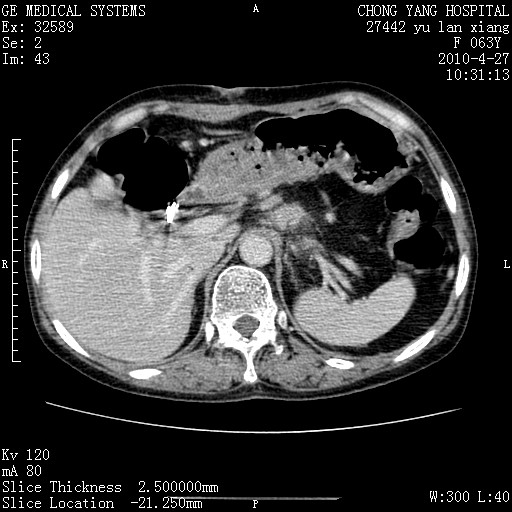

标题: CT26066:F63Y 上腹正中压痛半月,CA199:7400u/ml,MR示胰腺炎伴 [打印本页]

胰腺癌侵犯腹腔动脉干-分支、胃壁、左侧膈肌伴胰周及腹膜后淋巴结转移、胆囊切除术后。

胰腺癌侵犯腹腔动脉干-分支、胃壁、左侧膈肌伴胰周及腹膜后淋巴结转移、胆囊未显影。